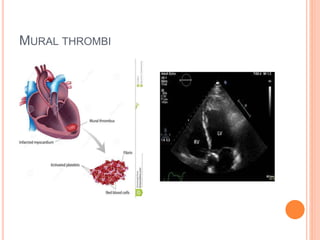

MURAL THROMBI

 Occurs in heart chambers or in the aortic lumen

 Precursors of Cardiac Mural Thrombi

 Abnormal myocardial contraction

 Arrhythmias

 Dilated cardiomyopathy

 Myocardial infarction

 Endomyocardial injury

 Myocarditis

 Catheter trauma

 Precursors of Aortic Thrombosis

 Atherosclerotic plaque

 Aneurismal dilation